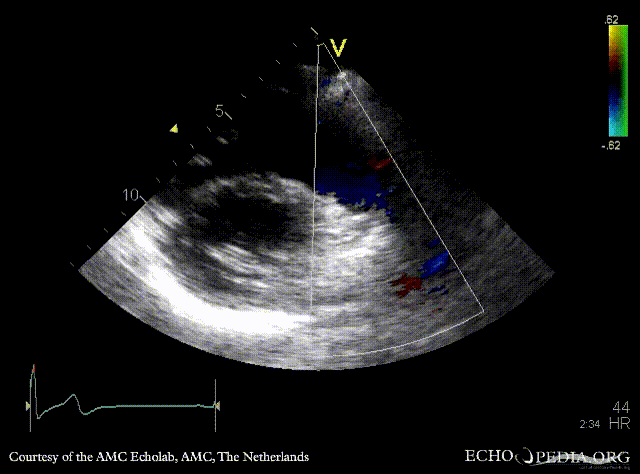

| PSAX with Color Doppler: dilated pulmonary artery in Marfan patient | Continuous-wave signal of transpulmonary flow |